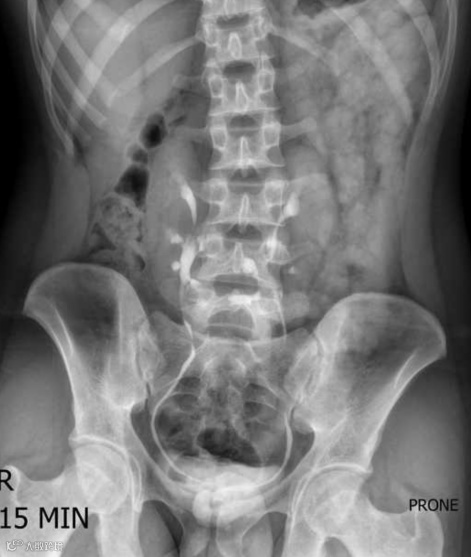

男,20岁,马蹄肾。KUB显示中线两侧各有一软组织肿块,中央可见峡部。注射造影剂后,肾盂肾盏系统的走向清晰可见。双肾下极最靠近中线,这与正常情况相反。双肾均呈旋转状,下极融合,在L3-L4水平形成峡部。